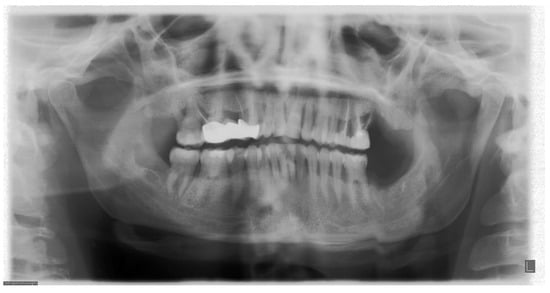

5. The Importance of Head Orientation

6.5. Position of the Cervical Spine